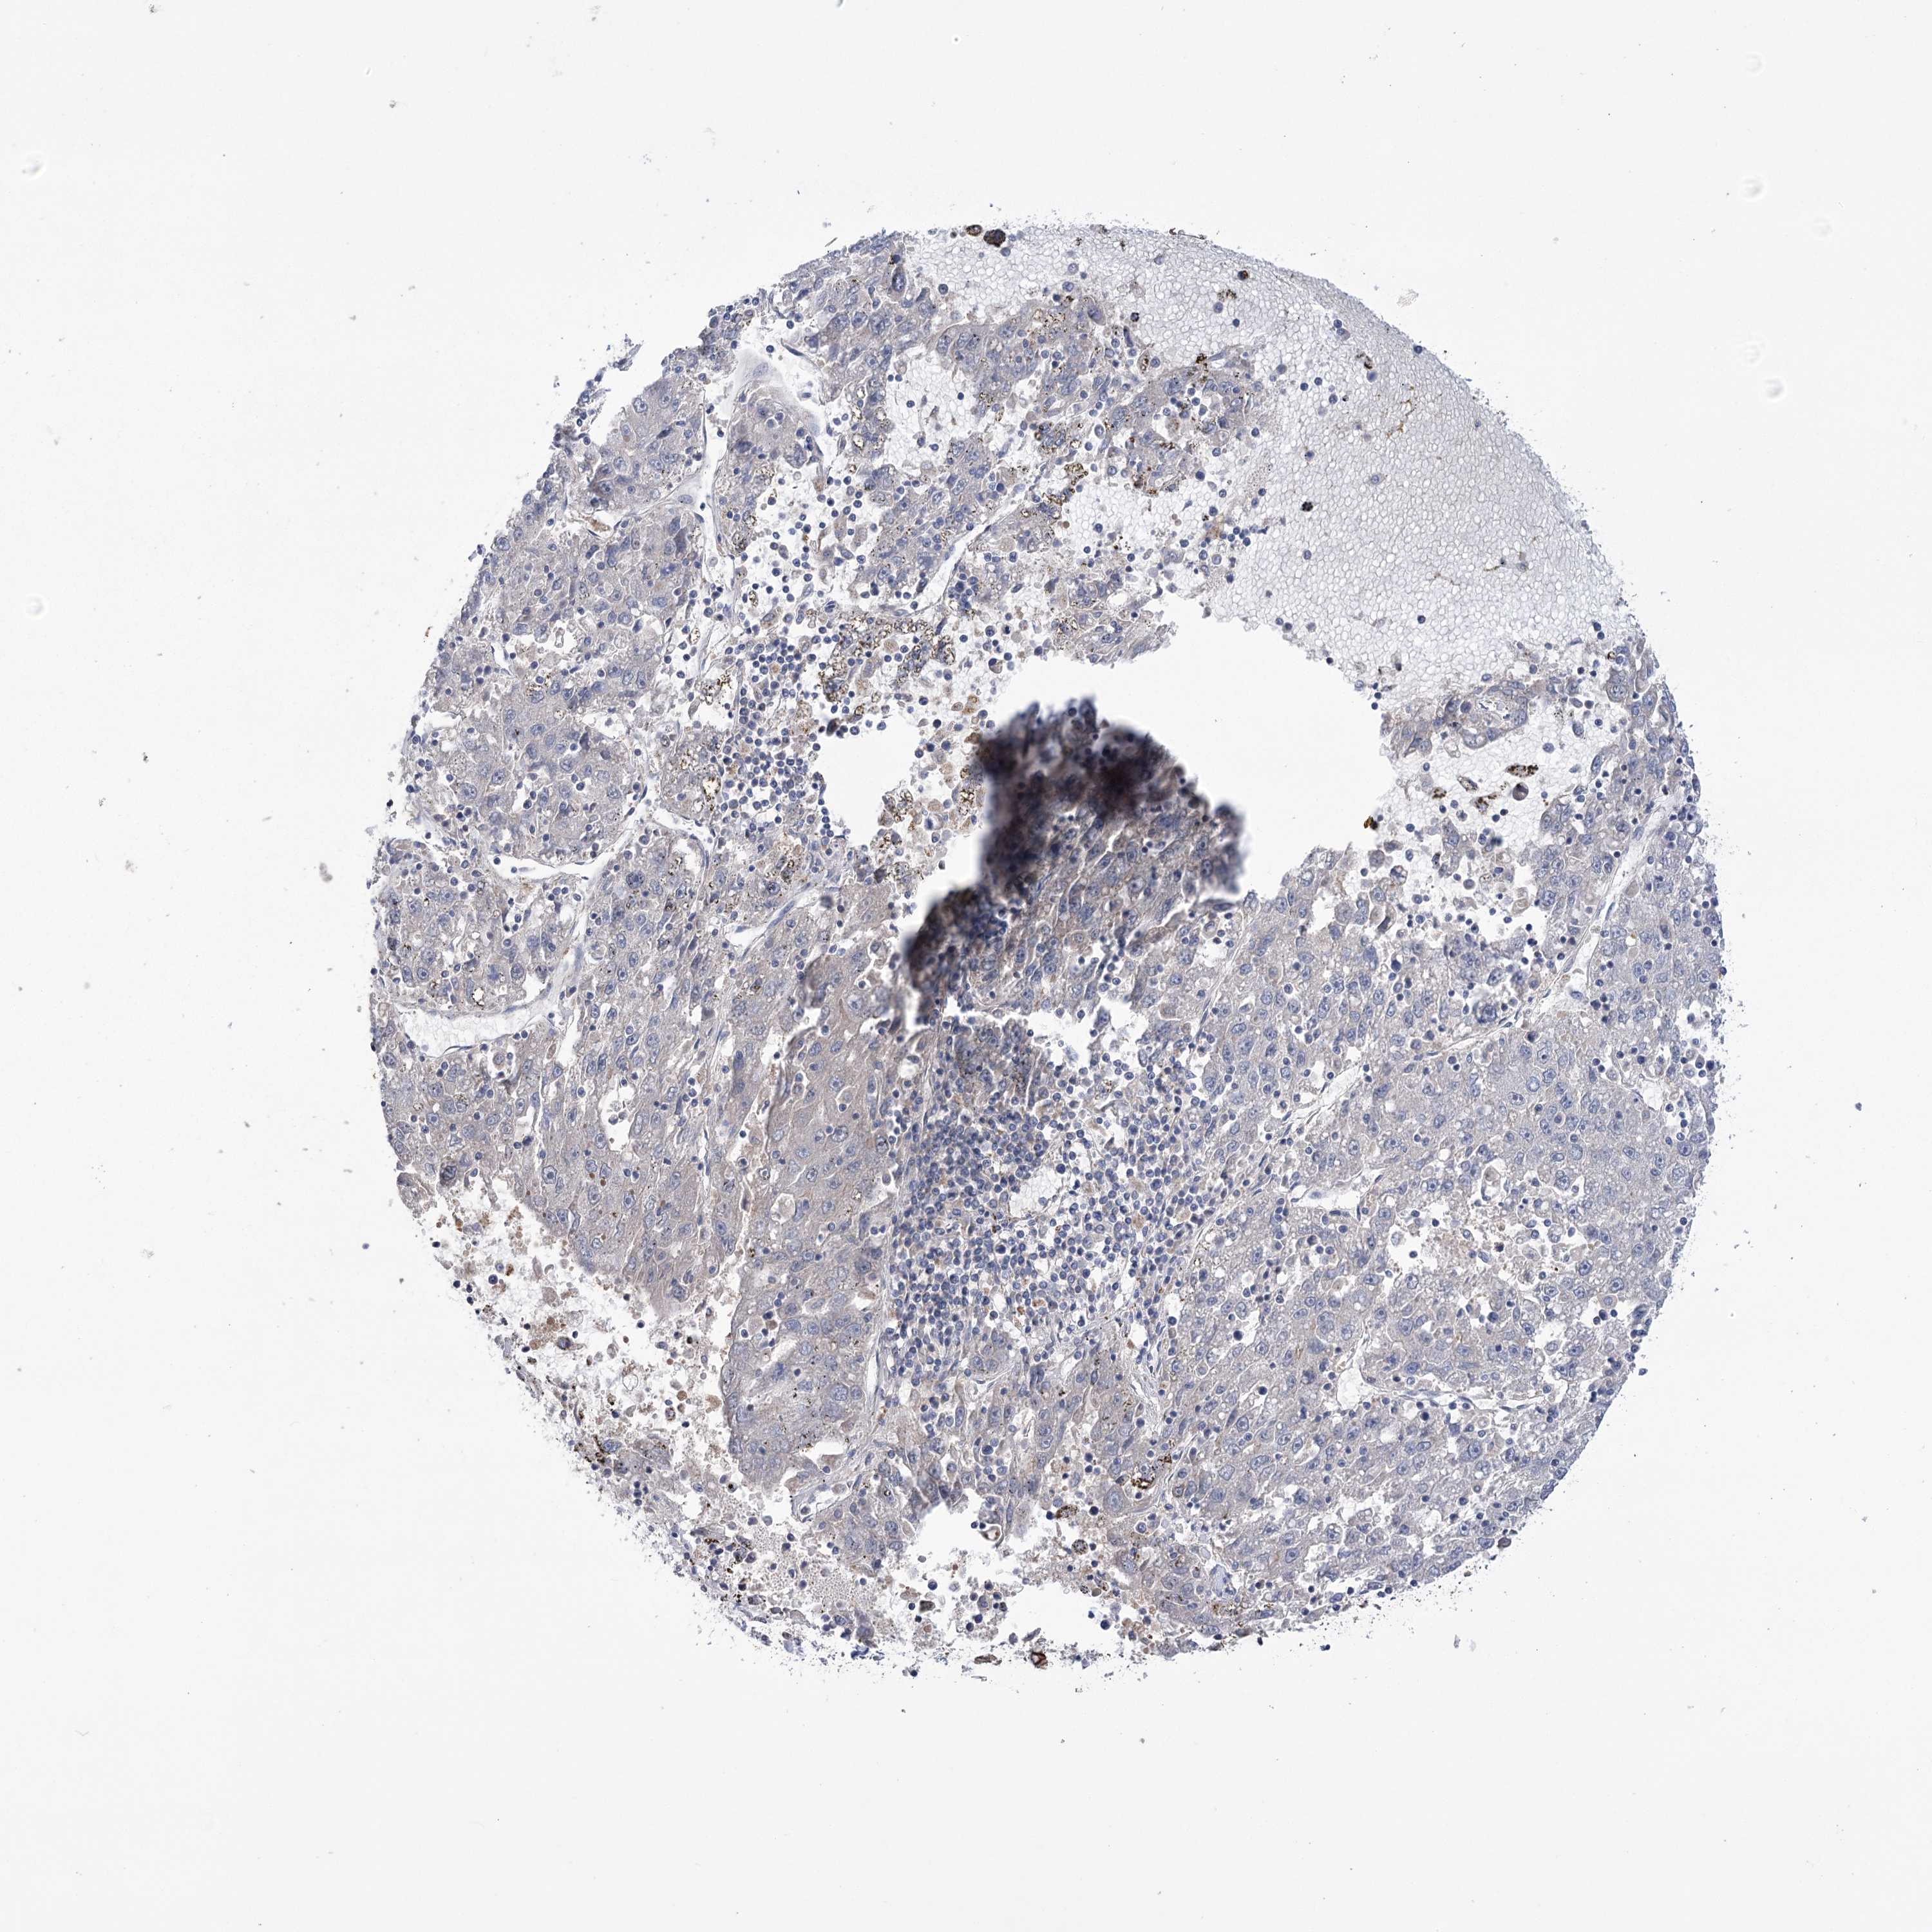

LIVER CANCER - Protein expressioni

A mouse-over function shows sample information and annotation data. Click on an image to view it in a full screen mode. Samples can be filtered based on level of antibody staining by selecting one or several of the following categories: high, medium, low and not detected. The assay and annotation is described here.

Note that samples used for immunohistochemistry by the Human Protein Atlas do not correspond to samples in the TCGA dataset.

Antibody stainingi

Antibody staining in the annotated cell types in the current human tissue is reported as not detected, low, medium, or high, based on conventional immunohistochemistry profiling in selected tissues. This score is based on the combination of the staining intensity and fraction of stained cells.

Each image is clickable and will lead to virtual microscopy that enables deeper exploration of all samples and also displays staining intensity scores, fraction scores and subcellular localization as well as patient and tissue information for each sample.

Antibody HPA038141

Antibody HPA038142

Staining

High

Medium

Low

Not detected

Intensity

Strong

Moderate

Weak

Negative

Quantity

>75%

75%-25%

<25%

None

Location

Nuclear

Cytoplasmic/membranous

Cytoplasmic/membranous,nuclear

Cholangiocarcinoma

Carcinoma, Hepatocellular, NOS